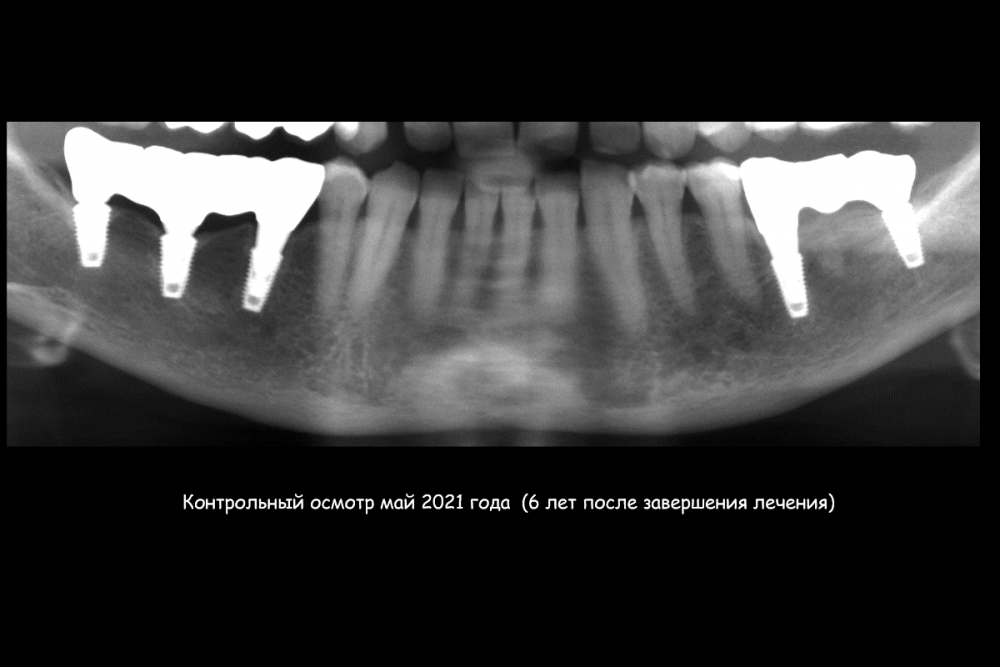

Карен Аванесов Опубликовано 23 июля, 2021 Поделиться Опубликовано 23 июля, 2021 (изменено) Этот пациент особо радует гигиеной на осмотрах, всегда очень чисто, приятно это. Важно когда пациент ответственный. По кейсу все на сгустке крови, без "проленового" рта. Изменено 23 июля, 2021 пользователем Карен Аванесов 6 3 1 Ссылка на комментарий